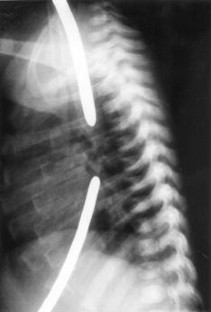

Fig. 2